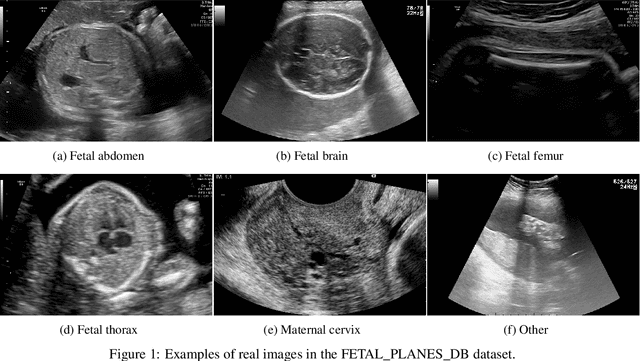

Abstract:Ultrasound imaging is widely used in medical diagnosis, especially for fetal health assessment. However, the availability of high-quality annotated ultrasound images is limited, which restricts the training of machine learning models. In this paper, we investigate the use of diffusion models to generate synthetic ultrasound images to improve the performance on fetal plane classification. We train different classifiers first on synthetic images and then fine-tune them with real images. Extensive experimental results demonstrate that incorporating generated images into training pipelines leads to better classification accuracy than training with real images alone. The findings suggest that generating synthetic data using diffusion models can be a valuable tool in overcoming the challenges of data scarcity in ultrasound medical imaging.